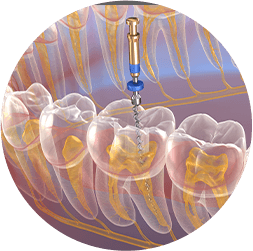

root canal therapy

If you develop an infection in one of your teeth you can experience pain and swelling and could even risk losing the tooth. Dr. Michel Raad and his team offer root canal therapy to relieve your discomfort and restore the health of your tooth. We will do everything we can to keep you comfortable and explain your aftercare needs.